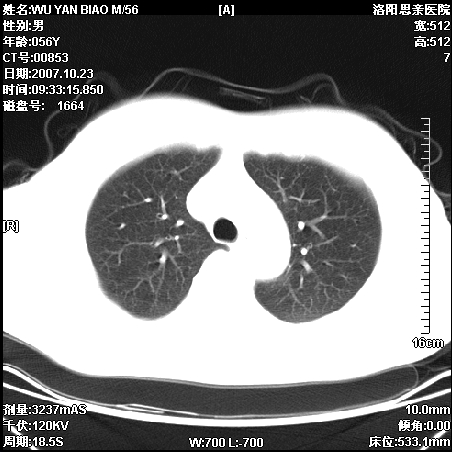

标题: CT10160:M56Y,体检发现,病人无不适,病人随访中 [打印本页]

标题: CT10160:M56Y,体检发现,病人无不适,病人随访中

后上纵隔占位,与肺交界清,宽基底附着脊柱,密度均匀,局部骨质无明确改变.

考虑;神经源性肿瘤,---起源交感n链?,不除外肠源性囊肿.

1、病灶在后纵隔脊柱旁沟内,此处是神经原性肿瘤的好发部位

2、病灶边缘光滑整齐,更说明病灶来于纵隔,由于有胸膜的包裹所以才导致这么光滑的边缘

3、病灶内的密度均匀